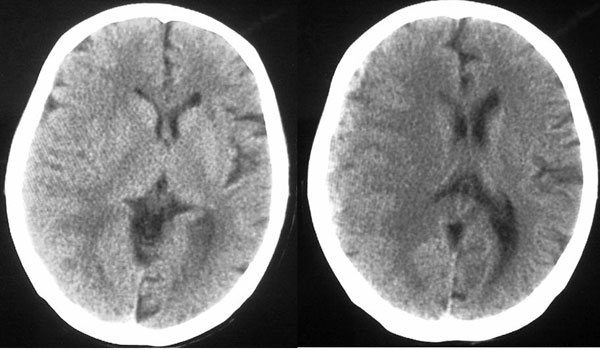

女87左下肢麻木,无外伤史

右颞顶部颅骨内板下新月形混杂密度影,右大脑皮层受压内移,考虑慢性硬膜下血肿,建议增强一下看看病灶,因为平扫好像显示的不是很好;左顶部软化灶

右侧大脑半球脑沟 脑裂变浅或消失,顶叶不规则低密度影,右侧侧脑室明显受压移位,中线偏移,右侧内板下新月形混杂高密度致密影,多考虑:慢性硬膜下血肿.必要时建议强化扫描.

右额颞顶部颅骨内板下方新月形混杂密度影,同侧灰白界限受压内移,右侧脑室呈受压性改变,中线结构左移;左顶叶扫及片状脑脊样低密度区,另可见部分脑沟增宽

ct印象:1.右额颞顶部慢性硬膜下血肿

2.左顶叶软化灶

3.脑部分萎缩